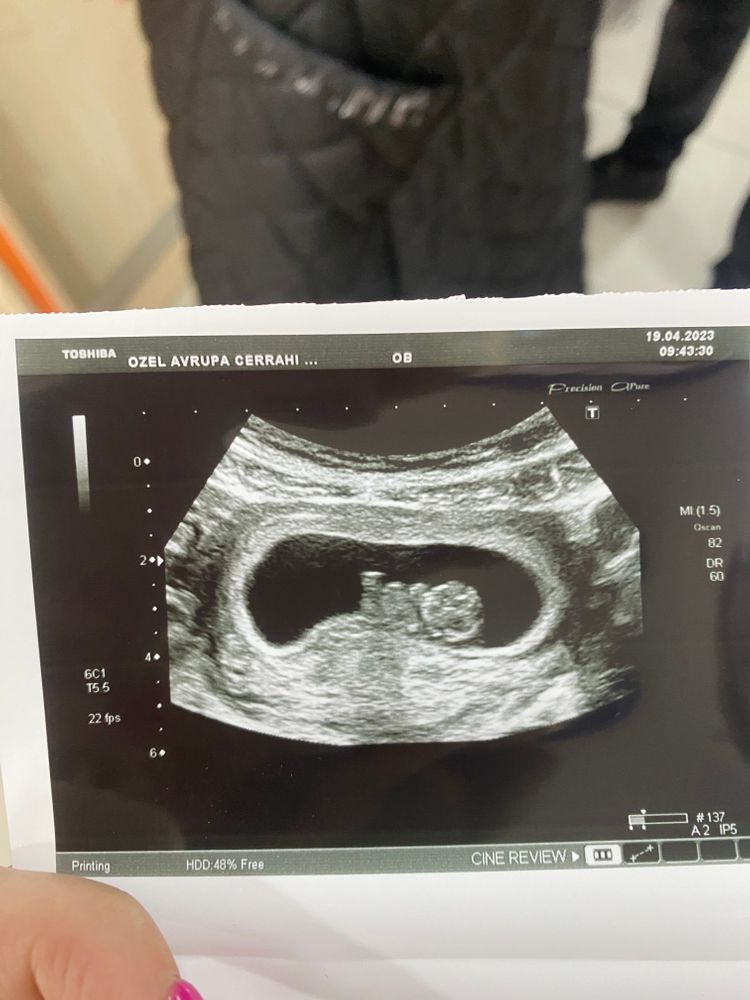

Изображение А какой у вас КТР? У меня в 9 и 3 на УЗИ за ручки и ножки вообще ничего не сказали, единственное,что сказали:"только начало все развиваться, ничего не видно,увидите все на скрининге "😅 Я даже не понимаю,как он лежит,у вас правда фото по ближе ..

Маша, у меня 22,4 мм, ровно на 9 недель) у вас? у меня сначала тоже как у вас фото было, малыш двигался и не смогли словить) может у вас так фотку так сделали??

Marina, у меня на 9 и 3 было 27 мм. Не знаю, возможно) меня посмотрели от силы минуты 3,хотя и в платную ходила,но была очередь,погоня за деньгами,видимо 😂

Маша, это все узи сегодня, сделали просто 3 фото) Изображение На этом фото тоже не понятно где и что😂